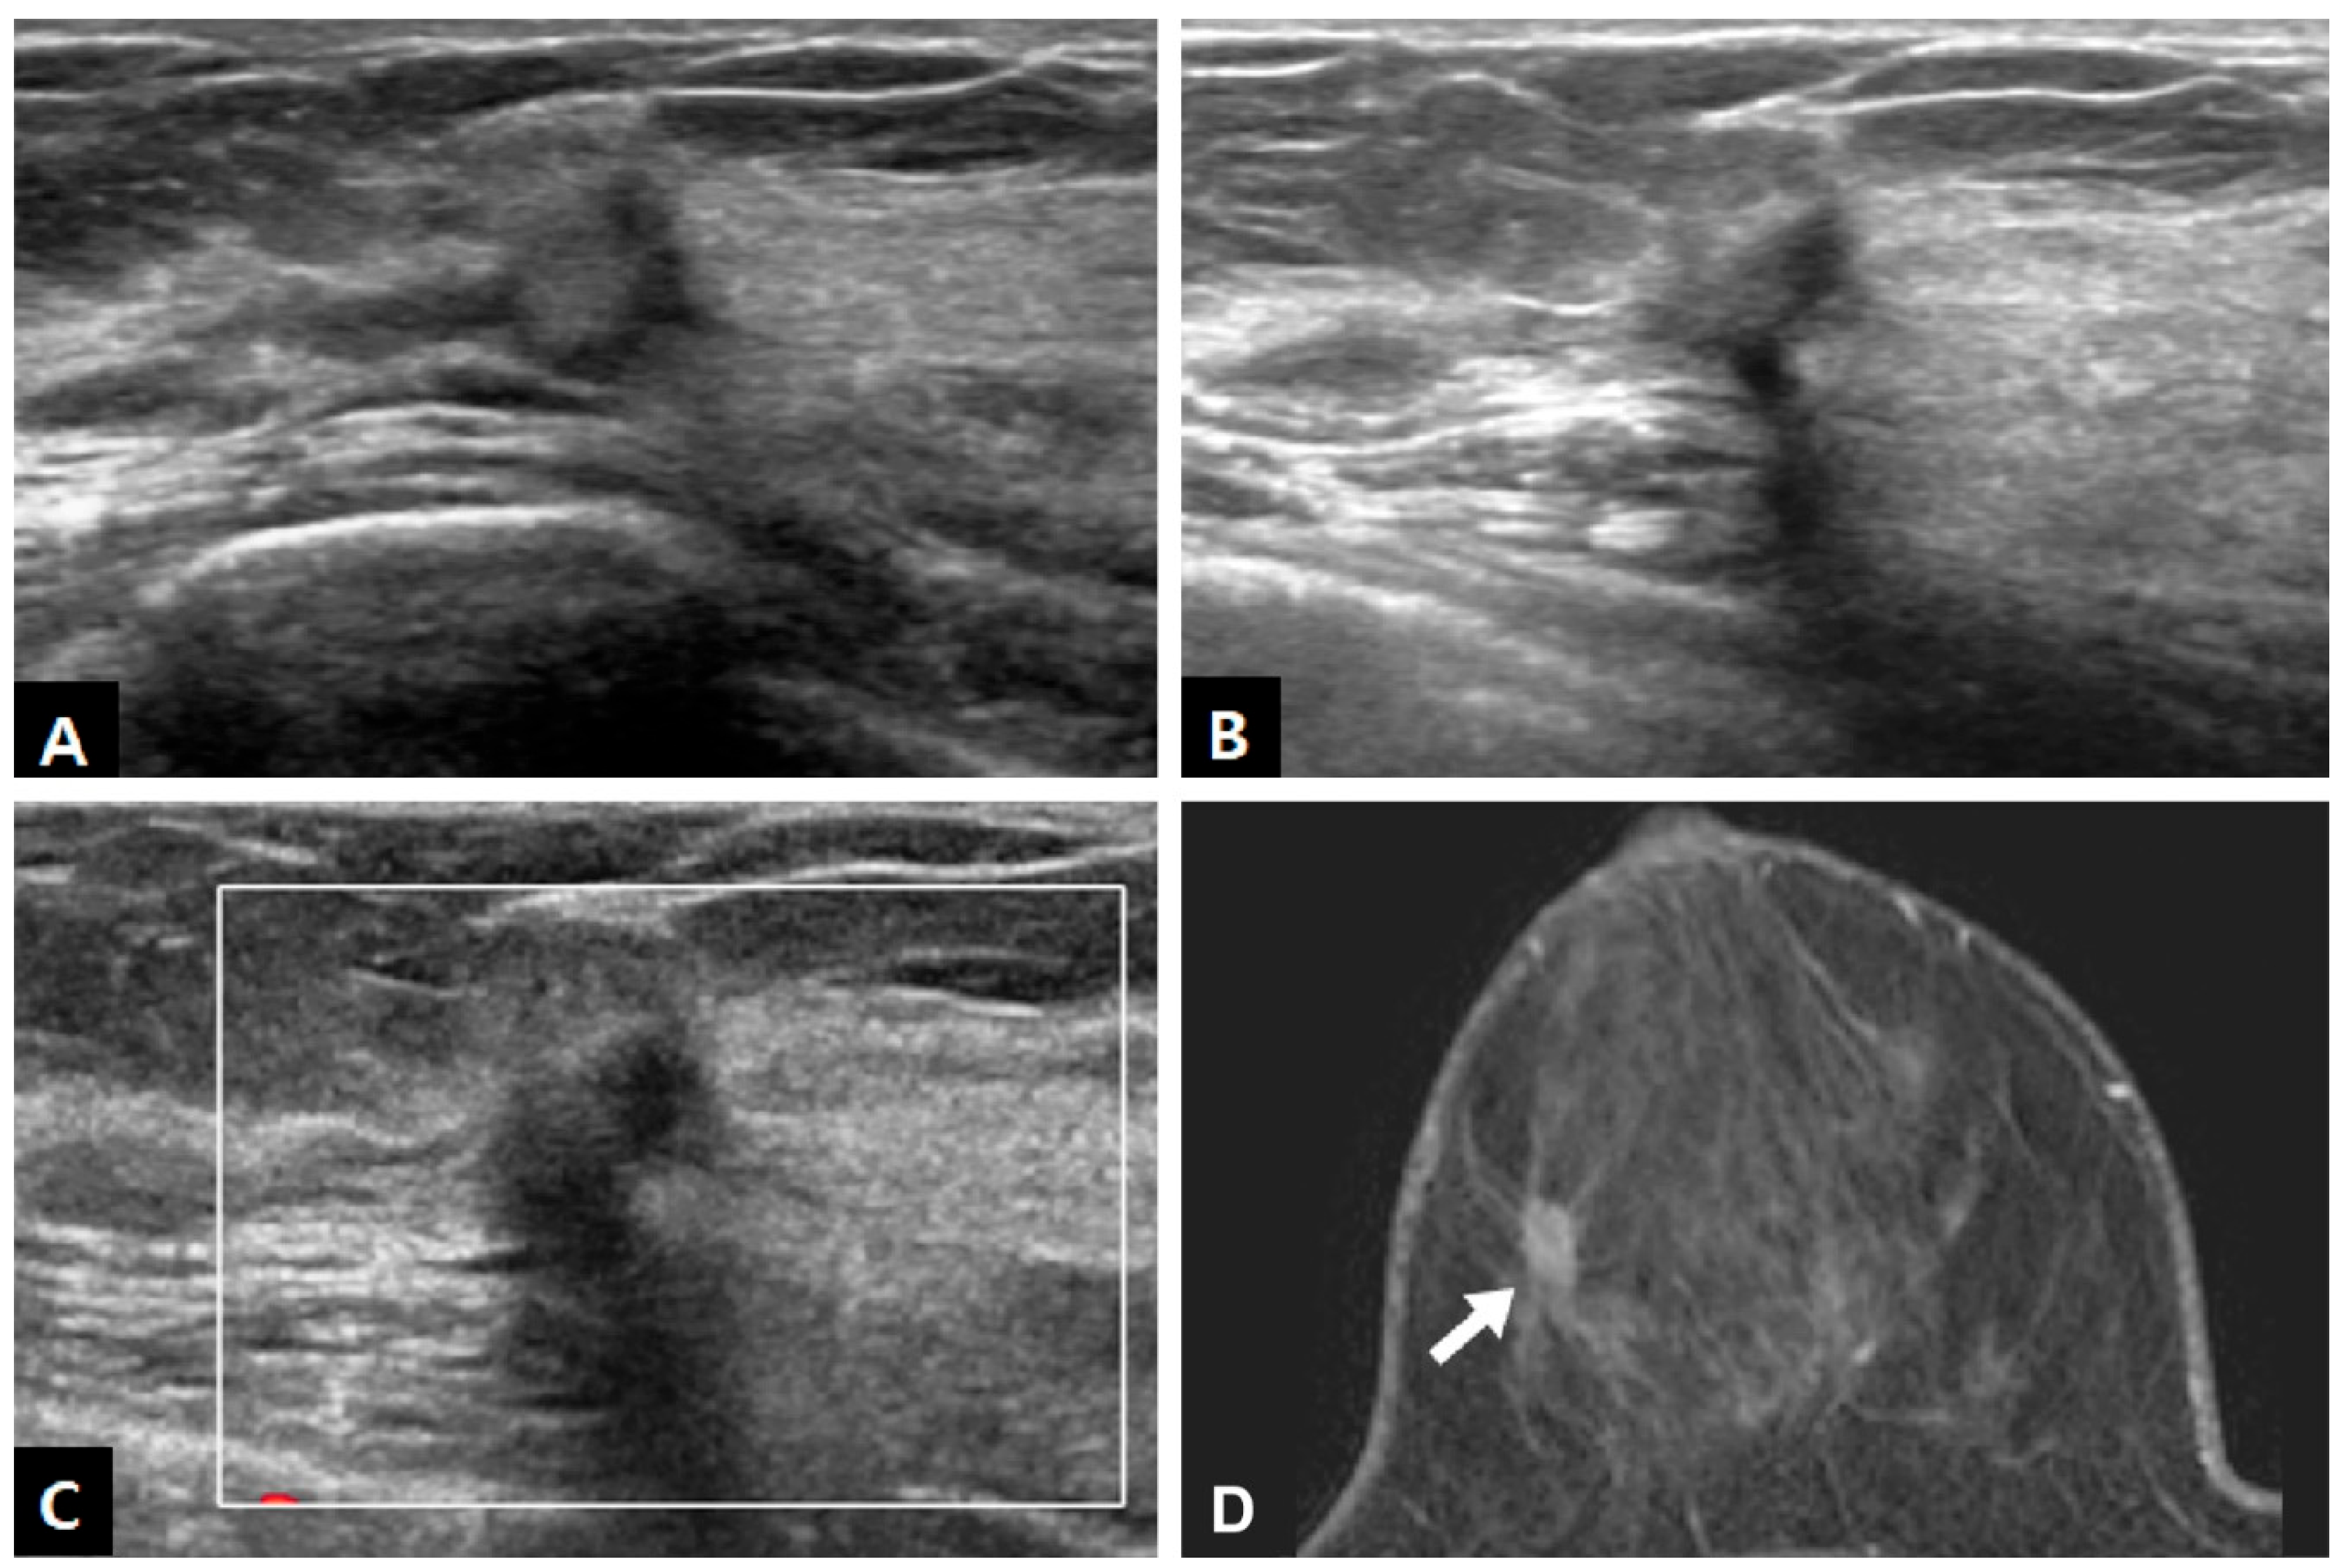

| Mass | 18/18 (100.0%) |

| Non-mass lesion | 0/18 (0.0%) |

| Size (cm, median) | 0.8 (0.6, 1.1) |

| Shape | |

| Round or oval | 9/18 (50.0%) |

| Tubular | 1/18 (5.6%) |

| Irregular | 8/18 (44.4%) |

| Margin | |

| Circumscribed | 8/18 (44.4%) |

| Not circumscribed | 10/18 (55.6%) |

| Echogenicity | |

| Hypoechoic | 3/18 (16.7%) |

| Isoechoic | 8/18 (44.4%) |

| Hyperechoic | 7/18 (38.9%) |

| Echogenic halo | 5/18 (27.8%) |

| Taller-than-wide | 11/18 (61.1%) |

| Posterior acoustic shadowing | 3/18 (16.7%) |

| Hypervascularity | 4/18 (22.2%) |

| Location | |

| Skin~subcutaneous layer | 3/17 (17.6%) |

| Subcutaneous layer | 2/17 (11.8%) |

| Subcutaneous layer~breast parenchyma | 9/17 (52.9%) |

| Breast parenchyma | 3/17 (17.6%) |

| BI-RADS category | |

| 3 | 7/18 (38.9%) |

| 4A | 9/18 (50.0%) |

| 4B | 1/18 (5.6%) |

| 4C | 1/18 (5.6%) |